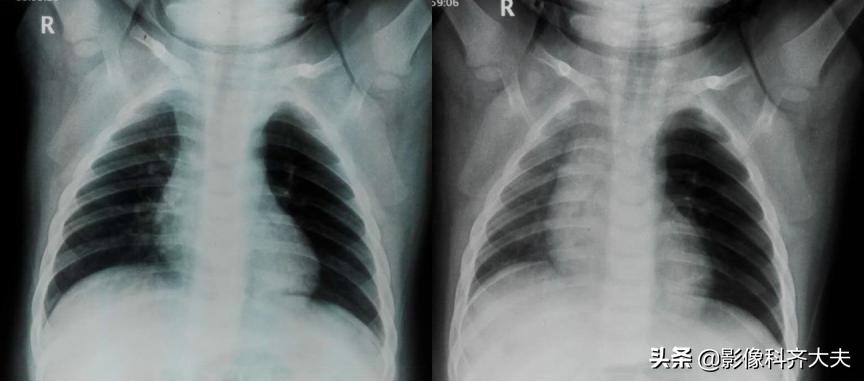

病例1、病史:女1岁6月,3天前有异物呛入史。

图1 图2

图1及图2左肺均有肺气肿表现;图1为吸气像纵隔居中,图2为呼气相纵隔向右侧(健侧)移位,即:纵隔摆动。提示左侧支气管有异物存在的可能。